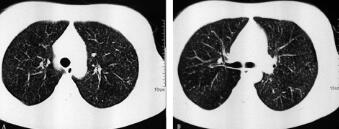

七、完善胸部CT的结果

胸部CT(图2)示双肺可见弥漫均匀分布的小粟粒状阴影。此时结合患者年轻、高热、用一般抗生素治疗无效,可诊断为急性血行播散型肺结核。但需注意,肺部的小粟粒状阴影应该与弥漫性泛细支气管炎、细支气管肺泡癌、粟粒型肺转移癌、间质性肺疾病等鉴别。脑脊液涂片抗酸染色可见结核菌。

图2